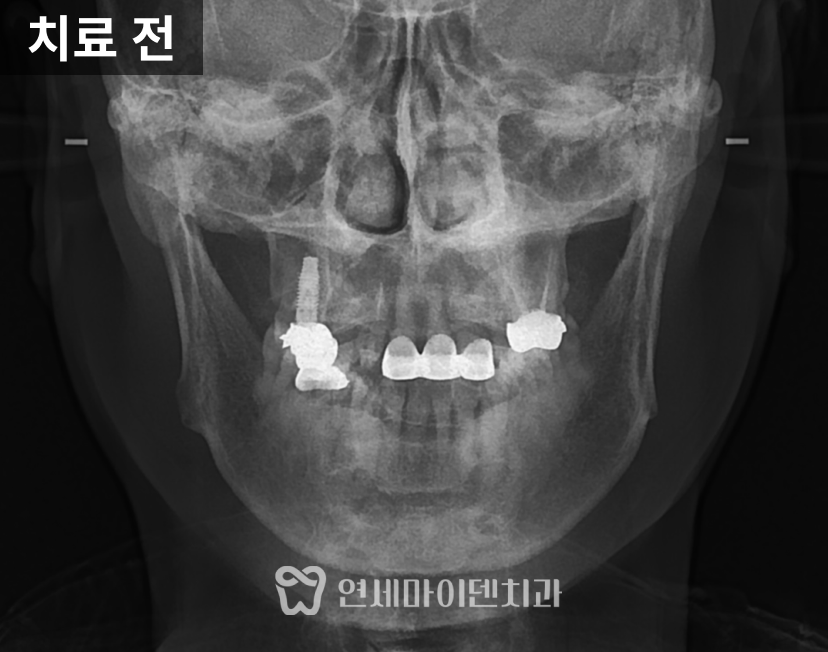

초기 진단에서 확인된 상태

중장년층 환자분들은 이미 과거에

보철 치료를 받아본 경험이 있는 경우가 많습니다.

이번 사례에서도 윗앞니 일부가

보철물로 연결되어 있었고,

아래 앞니는 배열이 고르지 못한 상태였습니다.

시간이 지나면서 기존 보철물의 심미성이 떨어졌고,

과거 교정 이후 다시 치아 사이에 틈이 생긴 점이

불편함으로 이어져 치료를 결정하게 되었습니다.

단순히 치아 배열만의 문제가 아니라,

기존 보철 상태와 현재의 교합 관계를

함께 살펴봐야 하는 상황이었습니다.

3급 부정교합의 특징과 잇몸 상태

검사 과정에서 치석이 많이 쌓여 있고,

잇몸이 전반적으로 부어 있으며

잇몸뼈가 내려간 소견이 확인되었습니다.

일부 치아 뿌리 끝에는

염증 소견도 동반되어 있었습니다.

방사선 사진에서는 윗턱보다 아래턱이

상대적으로 발달한 3급 부정교합(주걱턱) 이었고,

위턱 앞니는 앞으로 뻐드러진 상태였습니다.

이러한 골격적·치성적 특징은 치아 배열뿐 아니라

전체 교합 관계에도 영향을 주고 있었습니다.